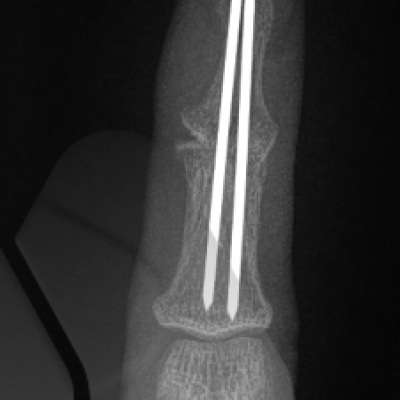

Joint replacement

Joint replacements can use many types of materials including silicone, metal and plastic and pyrocarbon. Silicone joint replacements have been used in the small joints of the hand since the early 1960’s. They have a long track record and have a predictable outcome and ability to exchange implants if they fail. Modern day Metal on plastic implants have evolved since 1979 and now resemble modern day “mini knee replacements”. Pyrocarbon is a newer material and has been used since 2000. It can be implanted as a total joint replacement or hemiarthroplasty (replacing only one damaged side of the joint). Most joint replacement surgeries provide good relief of pain whilst maintaining motion however it is difficult to reliably improve range of motion in very stiff fingers.